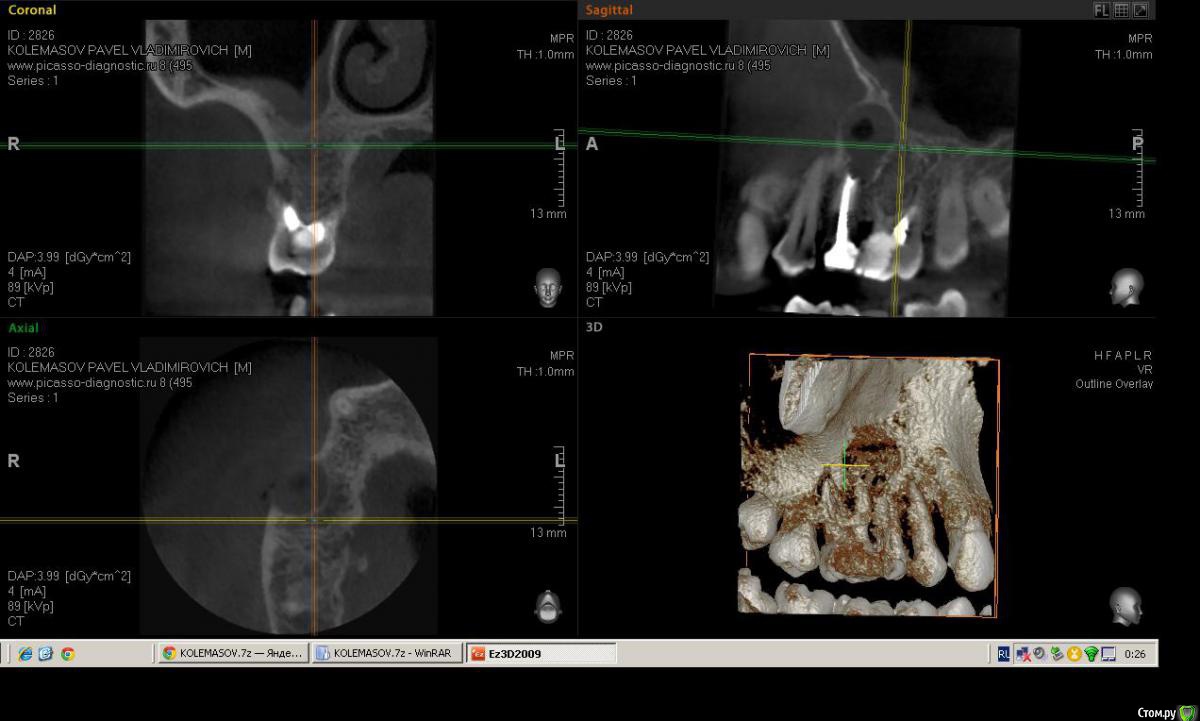

Salma Опубликовано 14 февраля, 2015 Поделиться Опубликовано 14 февраля, 2015 Пациент пришел с ноющими жалобами в области верхней челюсти справа, спасался обезболивающим несколько дней, говорит периодически болит, но сейчас разболелось сильно. Записался на вечер, на прием уже пришел немного припухшим. В полости рта, 16 зуб с глубокой полостью, перкуссия слабоболезненна, отечность болезненность по переходной, при надавливании выделяется гной, на небе в проекции верхушки небного корня тоже как бы формирующийся свищ с отделяемым. Делаем снимок прицельный, вижу разрежение в области 5-ки ( по словам пациента лечен более 10 лет назад). ДОговариваемся, что сегодня снимаем острую боль, а далее пациент делает кт и определяемся с судьбой зубов.Анестиеия, мех, мед,кальций. Делаю поласбляющий разрез, гной, нехило так проваливаюсь, кюретаж, дренаж. Собственно кт: (могу выслать ссылку на почту с кт) Ссылка на комментарий